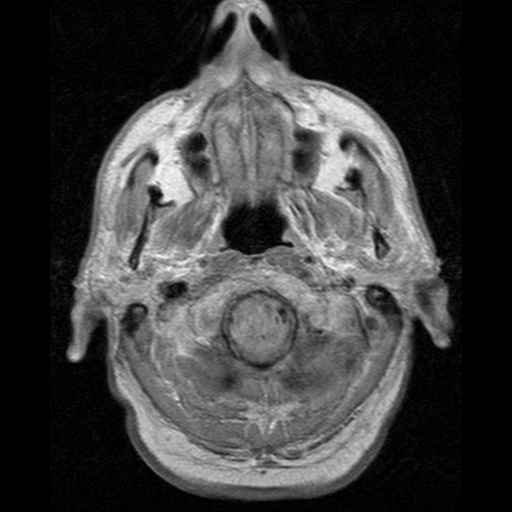

Jądrowy rezonans magnetyczny, RM, MRI, NMR

NPH_MRI_275.gifMój konik, pisałem o nim magisterkę. Nieinwazyjne badanie, tylko znacznie droższe od TK. Na animacji również projekcje poprzeczne mózgu. Porównajcie np. jak różne obrazy dają kości, oczy czy struktury w mózgu.

Zasada działania: kładziemy pacjenta w silnym, jednorodnym polu magnetycznym (przeważnie 1,5 lub 3T), co powoduje ustawienie spinu jądrowego protonów w jednym kierunku - można to rozumieć że jądra wodoru kręcą się w tę samą stronę. Następnie włączamy drugie pole magnetyczne, rotujące prostopadle do pierwszego z ustaloną częstotliwością (rezonansową, a jakże), co powoduje że jądra wpadają w precesję - wykonują ruch jak bączek pod koniec kręcenia, coraz silniej odginając się od “pionu”. Po wyłączeniu drugiego pola spiny powoli wracają do “pionu”. Drugie pole jest niejednorodne, więc różnie wpływa na protony, zależnie od ich położenia. Wykonując wiele takich “strzałów” z różnie zorientowanym polem magnetycznym jesteśmy w stanie zbudować obraz 3D. Dobra, ale co mierzymy? A pole magnetyczne wygenerowane przez te spiny, albo w momencie włączenia, albo wyłączenia drugiego pola.

Co widać: zależnie od sekwencji impulsów i momentu pomiaru, można zaobserwować zmiany funkcjonalne, zawartość wody w tkankach, rozróżnić istotę szarą od białej w mózgu, czy zlokalizować guzy. Głównie stosuje się do tkanek miękkich, ale zdarza się obrazować stawy czy kręgosłup. Jeśli zepniemy aparat z EKG, to możemy mieć świetny obraz pracy zastawek i komór serca - wymaga to wielu “strzałów” wykonanych w tym samym momencie cyklu pracy serca, więc badanie trwa długo.

Ograniczenia i zagrożenia: koszty, koszty, koszty. Musimy się odciąć od ziemskiego pola magnetycznego i zakłócaczy - pokój badań to klatka Faradaya z paroma wypustami (kable, wentylacja, chłodzenie). Magnesy chłodzi się ciekłym helem, który jest pieruńsko drogi. No i sam aparat żre prądu jak po⁎⁎⁎⁎ny, bo to wszystko elektromagnesy. Do tego hałas i czas trwania badania - elektromagnesy dudnią podczas ciągłego włączania i wyłączania, a badanie potrafi trwać nawet godzinę. Każde poruszenie się pacjenta ma wpływ na jakość obrazu. A, no i wszystkie elementy magnetyczne, jeśli obsługa ich nie zauważy i nie przykleja się do aparatu już na wejściu, to podczas badania grzeją się nieziemsko.

Ciekawostki: na Instytucie Fizyki Jądrowej PAN w Krakowie mają MRI o największym polu magnetycznym w Polsce, 9,4T. Otwór ma zaledwie 21cm, więc mieści się do niego najwyższej głowa lub kończyna, i jest wykorzystywany wyłącznie w badaniach naukowych. Z kolei na moim wydziale był MRI na stałych magnesach 0,2T, w którym miałem okazję leżeć, gdzieś mam zdjęcia.